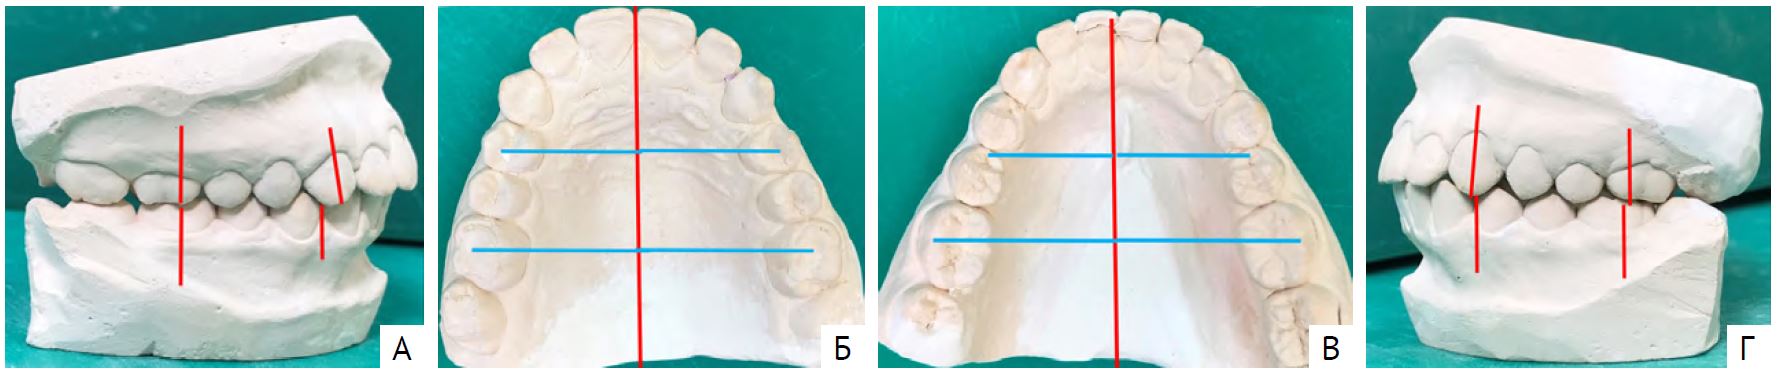

Составлен план лечения: «Расширить зубные ряды при помощи съёмных ортодонтических устройств с винтами и дистализировать первые постоянные моляры до их соотношения по I классу Энгля. Осуществлять контроль прорезывания клыков и премоляров. Исключить функциональные нарушения». Получен удовлетворительный результат лечения (рис. 4).

Рис. 4. Диагностические модели челюстей пациента Л. 13 лет: А — вид справа; Б — модель верхней челюсти; В — модель нижней челюсти; Г — вид слева

Достигнута нейтральная окклюзия. Устранено глубокое резцовое перекрытие. Положение резцов улучшилось, сохранялось тесное их положение. Создано место для прорезывания клыков и премоляров. Обращала на себя внимание задержка сроков прорезывания постоянных клыков, вторых премоляров и вторых моляров. Было рекомендовано исключить функциональные нарушения и «вредные привычки», посещать ортодонта 2 раза в год для контроля над формированием постоянного прикуса. Однако пациент не посещал ортодонта.

Выявили «вредную привычку» опираться рукой на подбородок. Родителям и пациенту разъясняли необходимость соблюдения правильной осанки, исключения «вредных привычек», функциональных нарушений [29]. На диагностических моделях челюстей (рис. 5) определили правильные фиссурно-бугорковые контакты боковых зубов. Перекрытие нижних резцов оказалось больше 1/2 высоты коронок сопровождалось их тесным положением и тортопозицией.

Рис. 5. Диагностические модели челюстей пациента Л. 15 лет: А — вид справа; Б — модель верхней челюсти; В — модель нижней челюсти; Г — вид слева